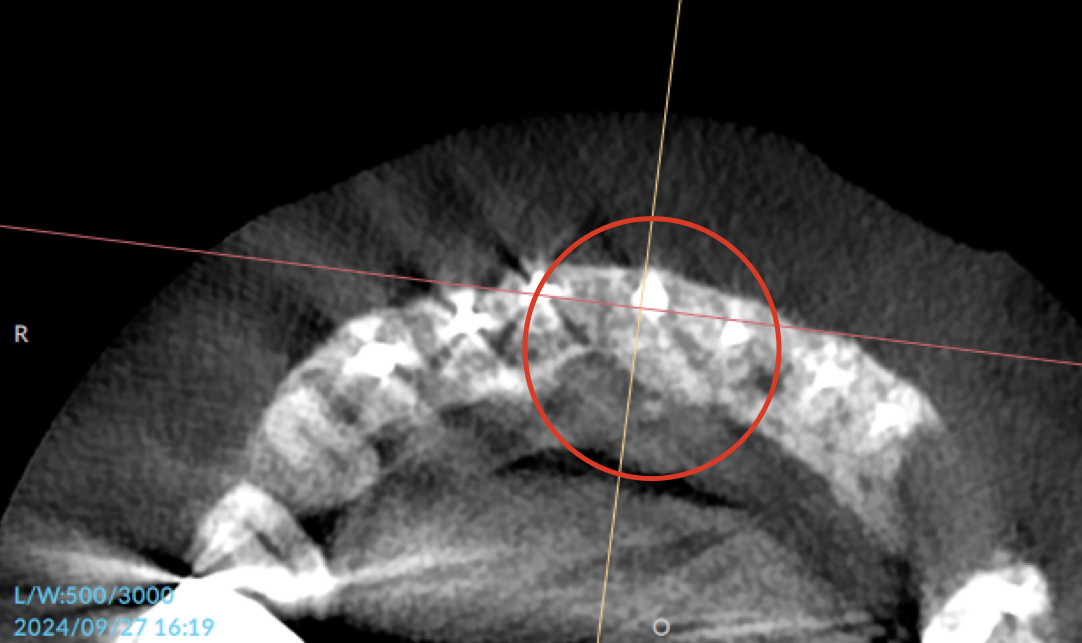

根管治療、そして骨補填剤を駆使して1年ほど。

喪失していた骨も再生し、見違える状態にまで回復しました。

これは治療をした私自身、とても驚いています。

CT②